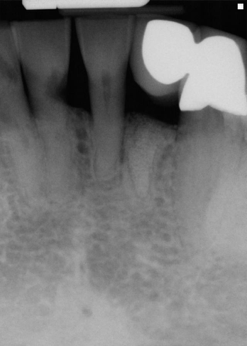

The young man was evaluated at 2 weeks (Figure 25 and Figure 26) and again at 6 weeks (Figure 27). The remaining natural teeth and the implant were stable. The natural teeth had a reduction in mobility to plus 1 at most. The patient's expectation was met. The soft-tissue element of his smile was maintained, and the patient is considering more cosmetic dentistry to optimize his smile. At 16 weeks postoperatively, the radiograph suggested that the digital workflow provided a great benefit to the patient and reduced the amount of chair time in the dental practice, with help from digital technology and the dental laboratory (Figure 28).

Fig 28. Postoperative radiograph at 16 weeks.

Figure 28